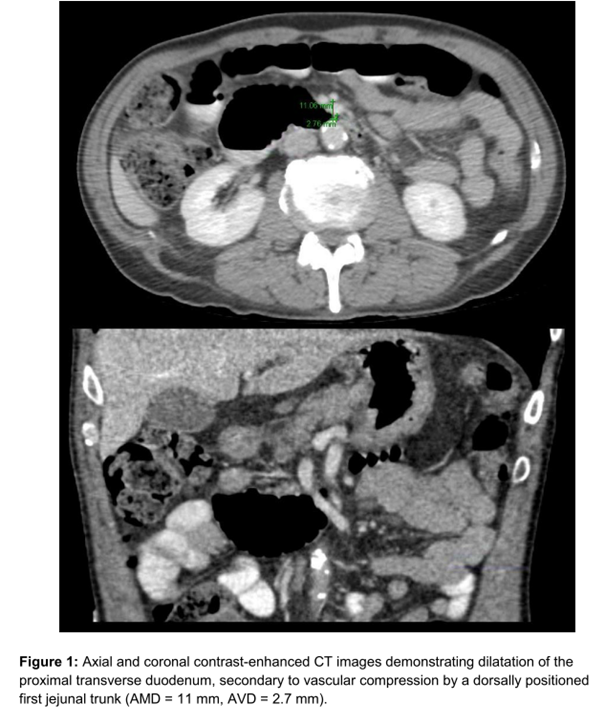

Image: from Yetişir [1] shows an interposition of the mesenteric vein in between the superior mesenteric artery and the duodenum

The paper from Yetişir [1] shows the mesenteric vein interposed between the superior mesenteric artery and the duodenum. Consequently, both vessels exert compression on the duodenum. However, the images supporting the diagnosis in the paper suggest that some of the compression attributed to the superior mesenteric vein may actually originate from the jejunal vein branch behind the superior mesenteric artery. This condition is not uncommon. Nevertheless, the paper only contains one image demonstrating the dumbbell-shaped mesenteric vein dorsal to the superior mesenteric artery.

This dumbbell shape however may be the origin of the jejunal vein. On the other hand the mechanism of course to compress the duodenum is similar to my own observation described above. The treatment of the reported case was a laparoscopic duodenal jejunostomy. This may be the right choice in this peculiar topographic situation where a interposition of a external shield around the left renal vein would like to compress the soft superior mesenteric vein against the more rigid superior mesenteric artery. The pure transposition of the superior mesenteric artery which is another option with the classic superior mesenteric artery syndrome would likely not work in this case since the artery is not the only compressing structure despite certainly contributing to the pressure transmitting it via the interposition superior mesenteric artery vein onto the duodenum.